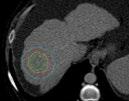

Quantitative CT Analysis of Hepatocellular Carcinoma Nodules in Liver Transplant Candidates: Impact of Volume of Interest and Contrast Phase on Recurrence Prediction

Keywords: Contrast, hepatocellular carcinoma, liver, recurrence, radiomics, segmentation, transplant, variability.

BACKGROUND AND AIMS

Liver transplantation is the primary treatment for patients with early-stage hepatocellular carcinoma (HCC), which is not eligible for resection.1 However, even when Milan criteria are met, disease recurrence occurs in up to 16% of cases, resulting in a decrease in disease-free survival to 40%.2

Therefore, having preoperative knowledge of the likelihood of recurrence would assist in selecting the most suitable liver transplant recipients, potentially avoiding unnecessary surgeries, and improving patient prognosis and organ allocation. In this context, radiomics, which involves high-throughput data extraction from medical images, holds great promise.3 However, there is ongoing debate regarding the optimal data selection strategy, as factors such as the choice of contrast phase and volume of interest (VOI) can significantly impact radiomic analysis results.4-6 Therefore, the authors’ study aimed to investigate how these factors influence radiomic features (RF), to identify the optimal combination for predicting HCC recurrence in liver transplant candidates.

MATERIALS AND METHODS

Liver transplant candidates from 2010–2019, with waitlist placement CT scans showing nodules suspicious for HCC, according to the Liver Reporting and Data System (LI-RADS) criteria7 (LR-4/-5), and histologically confirmed after the transplant, were retrospectively included. Patients who had previously undergone locoregional procedures, exhibited tumour in vein, or had poor image quality were excluded from the analysis. HCC nodules were contoured

Redundancy: InterVOI: 14–26%

Interphase: 16–34%

Autocorrelation: 4%

AP: arterial phase; AUC: area under the curve; CI: confidence interval; DP: delayed phase; No: number; PVP: portal venous phase; RF: radiomic features.

Segmentation Feature Selection Modelling Arterial phase Portal venous phase Delayed phase = Nodule = +5 mm (PT_5) = +10 mm (PT_10) = +15 mm (PT_15) = Background Nodule AP-PVP PVP-DP AP-DP 0% 0% 20% 20% 40% 40% 60% 60% 80% 80% 100% InterVOI MRC >10% Interphase MRC >10% 100% PT_5 PT_10 PT_15 AUC (CI: 95%) P value Pseudo-R2 No. of RFs AP_Nodule 0.77 (0.65–0.90) 0.020 0.23–0.32 8 AP_PT_5 0.90 (0.83–0.97) <0.001 0.33–0.44 8 AP_PT_15 0.88 (0.76–1.00) <0.001 0.36–0.46 12 AP_Nodule_Norm 0.87 (0.75–0.98) <0.001 0.34–0.44 9 DP_Nodule_Norm 0.86 (0.77–0.95) <0.001 0.24–0.35 11 AP_PT_5_Norm 0.88 (0.80–0.97) <0.001 0.31–0.44 8 PVP_PT_10_Norm 0.88 (0.77–0.99) <0.001 0.35–0.45 8 PVP_PT_15_Norm 0.77 (0.65–0.89) 0.002 0.13–0.24 5

Figure 1: Workflow and results from the radiomic analysis of hepatocellular carcinoma nodules and peritumoural regions extracted from the waitlist placement CT scans of liver transplant candidates to predict disease recurrence.

■ = Arterial ■ = Delayed ■ = Portal

■ = Nodule ■ = PT_10 ■ = PT_15 ■ = PT_5

across arterial, venous, and delayed phases, with or without peritumoral region of 5, 10, and 15 mm. An area of ‘background’ liver parenchyma, distant from the lesions, was also segmented in each phase.

A total of 107 RFs, both directly extracted from segmentations, and normalised for the ‘background’ parenchyma, were obtained using PyRadiomics (Python Software Foundation, Beaverton, Oregon, USA). The normalisation was conducted by calculating the ratio between the RFs extracted from the VOI, and those extracted from the background segmentation. These features were then compared with each other for inter-VOIs and inter-phase relative change, while autocorrelation was assessed using Spearman’s rank correlation coefficient. RFs with relative change <10% and rank correlation coefficient >0.90 were considered non-informative. Informative RFs with different distribution in patients with and without posttransplant recurrence were selected to build multiple logistic regression models. Prediction of post-transplant recurrence was assessed by comparing the areas under the curve from receiver operating characteristic analysis and goodness-of-fit, expressed as the value range of Tjur’s, McFadden’s, and Nagelkerke’s R2 .

RESULTS

The CT scans of 53 patients were selected, resulting in a total of 1,032 segmentations from 86 nodules, with eight (15%) recurrence cases. When varying VOIs and phases, the proportion of noninformative RFs, indicating insignificant differences between the VOI and liver background, were 14–26% and 16–34%, respectively, while 4% of RFs showed autocorrelation >0.90.

The selected informative RFs allowed the building of eight predictive models with adequate performance and goodness-of-fit,

each comprising 5–12 RFs, with an area under the curve of 0.77–0.90 (p<0.02) and pseudo-R2 values of 0.13–0.46. A predominance of models derived from the arterial phase was observed, utilising the nodule with or without a 5 mm peritumoral region as the VOI, followed by the venous phase, including a 10–15 mm margin after normalisation (Figure 1).

CONCLUSION

Selection of optimal VOI and contrast phase combination is critical to maximise post-liver transplant HCC recurrence prediction using quantitative CT imaging. Specifically, segmenting the nodule, eventually including a 5 mm peritumoral region, during the arterial phase, or the nodule with a 10-15 mm margin during the venous phase after normalisation against the liver background, appeared to be the most promising strategy.●